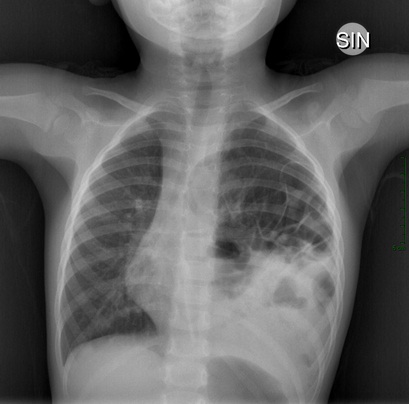

A., una bimba di 2 anni, giunge in Ambulatorio di Accettazione Pediatrica perch� da qualche giorno ha febbre e fa fatica a respirare. Era stata da poco vista dalla sua Pediatra che dubbiosa aveva richiesto una radiografia del torace. Mah? Vediamo cosa ci suggerisce la nostra visita. Curiosi ci affrettiamo a visitarla. A. presenta modesti rientramenti al giugulo e respiro un po� appoggiato, all�emitorace sinistro l�ingresso aereo � ridotto con ottusit� alla base. Ma qualcos�altro non ci convince. L�itto sta nel mezzo! I dubbi si moltiplicano e ci arrendiamo al fatto che un po� di radiazioni questa volta ci potrebbero essere d�aiuto. E non ci sbagliavamo: �emitorace sinistro occupato da anse intestinali. Sbandamento verso destra del mediastino� (Figura 2).

Figura 2.

Dopo un breve momento di stupore, nelle nostre menti si fa spazio un quesito. Possibile che fino ad allora l�intestino �fuori sede� non avesse mai dato segno di s�? I genitori della piccola paziente ci raccontano che A. � una bambina vivace e a parte �le solite infezioni da nido� � sempre stata bene. Agli occhi di noi �giovani medici� questo decorso � alquanto strano. Siamo tutti concordi e dopo un rapido consulto coi cugini chirurghi A. � gi� in sala operatoria per rimettere in ordine le cose. Anche questa volta tutto � tornato al suo posto e abbiamo tirato un sospiro di sollievo.